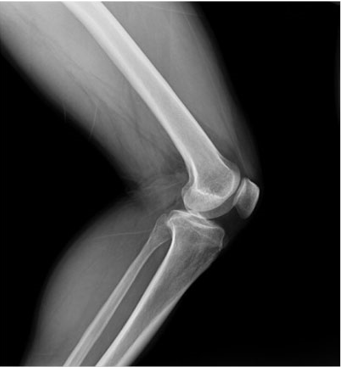

臨床圖片